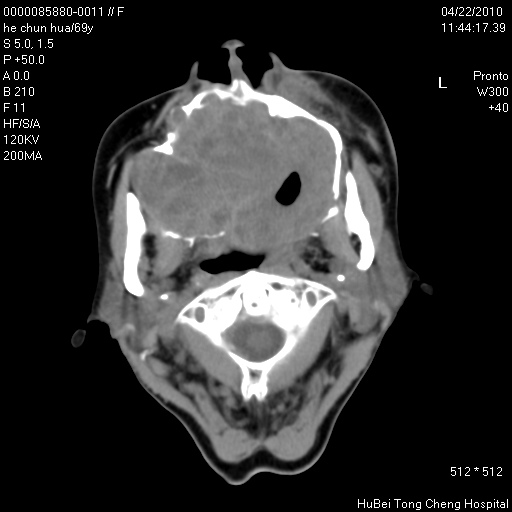

标题: CT25937:女,69Y

硬腭部包块十余年,渐进性增大。